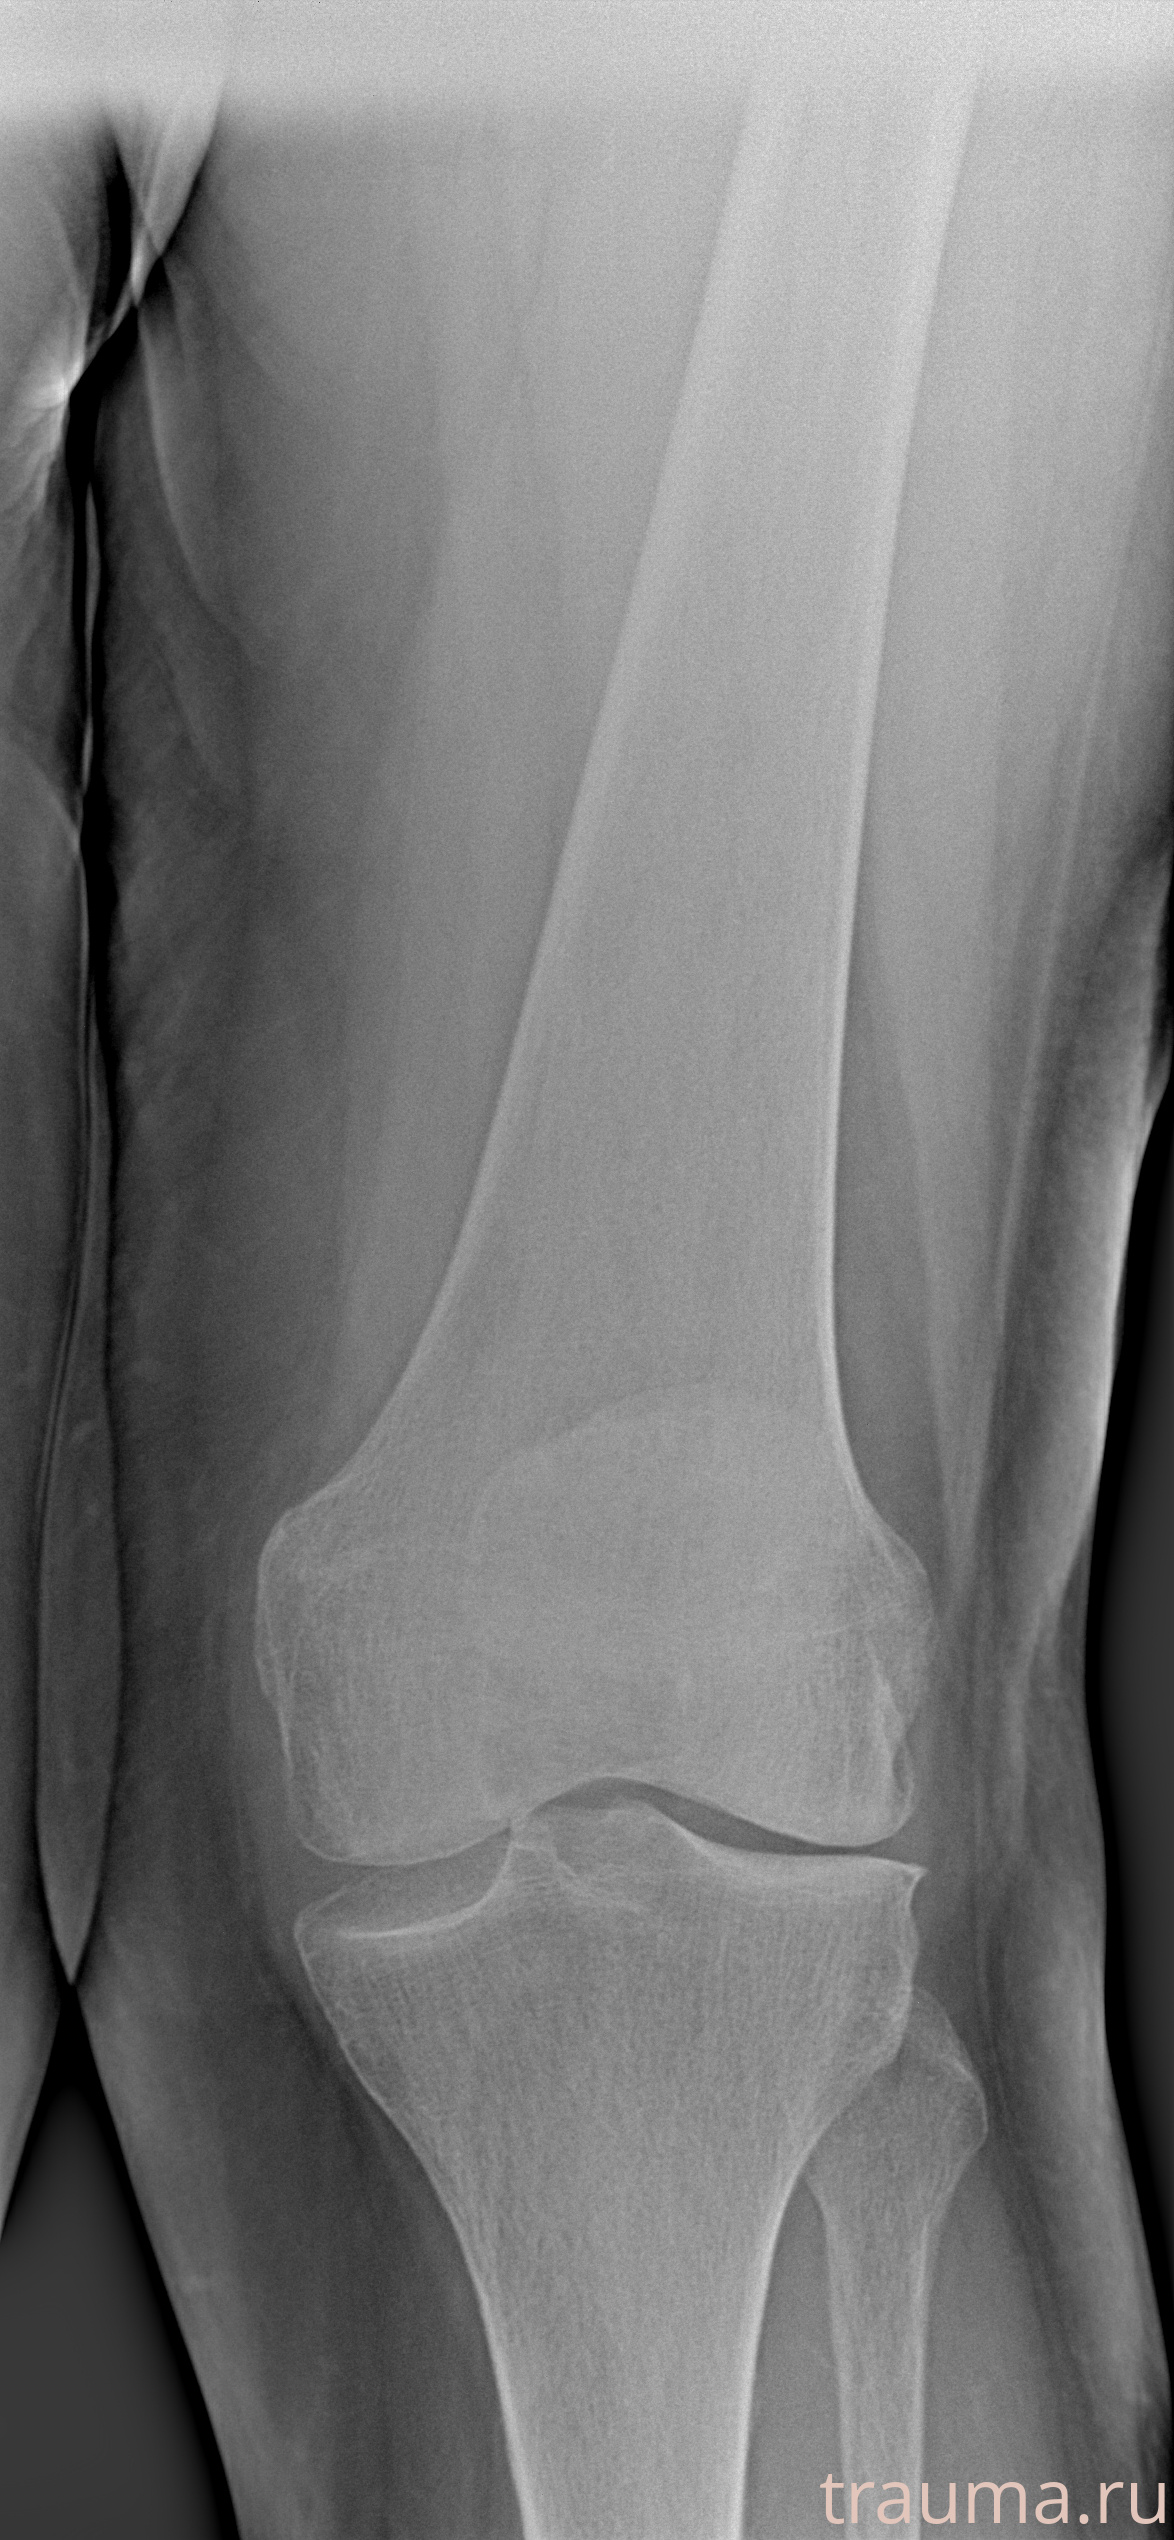

Рентгенограммы

Левая

Рентген на дому: по вашему адресу приезжает врач-рентгенолог, травматолог-ортопед с мобильным рентгеновским аппаратом, проводит диагностику травмы или заболевания, делает необходимые рентгенограммы, дает рекомендации по дальнейшему лечению. Получить качественные снимки в домашних условиях возможно благодаря уникальной методике, разработанной МосРентген Центром для института  Склифосовского